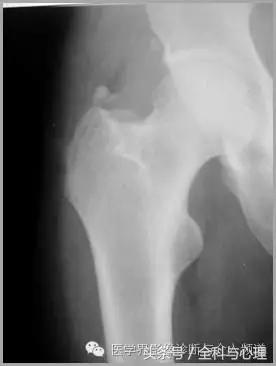

大粗隆滑囊炎